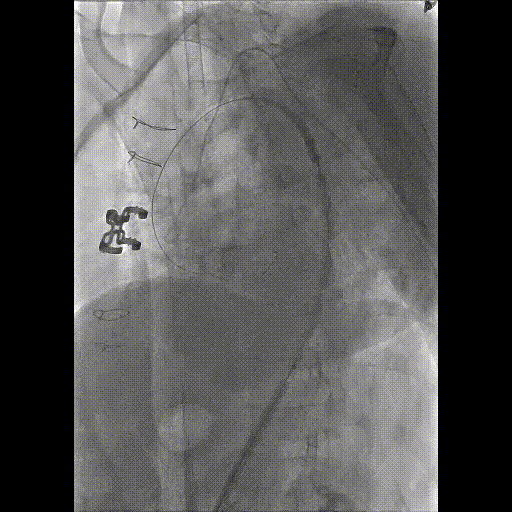

★ Case 3

男性,61岁,Bentall术后1年,主动脉弓部夹层;

既往史:高血压3级;

夹层动脉瘤CTA:A型主动脉夹层术后残余主动脉弓部夹层,头臂干及左颈总动脉根部夹层累及,向下累及胸腹主动脉至髂血管平面。

术前影像

造影后经股动脉导入并释放限制支架

经股动脉导入主体支架,抓捕无名动脉预留导丝,支架导入升主动脉

造影定位后释放主体支架

经股动脉依次超选导入分支支架,释放并球囊扩张,术毕造影

术后复查

三个穿刺点(双侧肱及单侧股动脉)无需颈部切口/穿刺

First In Man早期结果